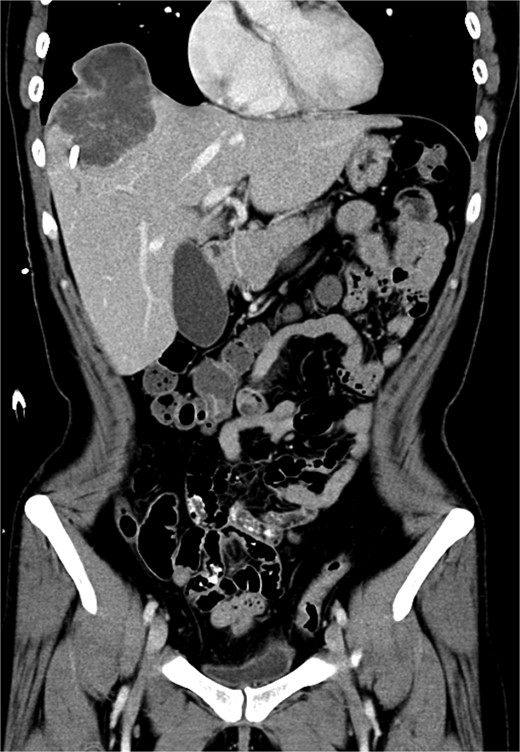

A 35-year-old woman with a history of prior alcohol use and tobacco smoking presented with a 2–3 month history of right shoulder pain, followed by generalized weakness, poor appetite, and abdominal discomfort. She also reported right rib pain, unintentional weight loss (3 kg within 3 months), and night sweats. She denied fever, upper respiratory infection symptoms, chest pain, shortness of breath, abdominal pain, dysuria, or diarrhea. Initial investigations at another hospital, including a chest X ray (Fig. 1), abdominal computed tomography (CT) scan, revealed a hepatic mass at segment 8 (S8). Tumor markers, hepatitis B virus, and hepatitis C virus serologies were negative.

Chest X ray image of sarcomatoid cholangiocarcinoma with direct invasion into the diaphragm and lung.

Upon admission to the GI ward, a repeat abdominal CT scan suggested a possible liver abscess. Drainage was performed on September, 2024, and empirical antibiotic therapy with ceftriaxone and metronidazole was initiated. Despite initial drainage and antibiotics, the patient continued to experience intermittent fever. A subsequent CT scan revealed a heterogeneous lesion measuring ~7.5 × 8.5 cm at S8 (Figs 2 and 3). A sono-guided liver biopsy was performed, and the pathological report indicated hepatic sarcomatoid carcinoma with variable positivity for CK and CK7, and negativity for CK20, glypican-3, ERG, and CD34 stains, suggesting a possible cholangiocarcinoma component. A general surgery (GS) consultation was obtained for suspected liver tumor management.